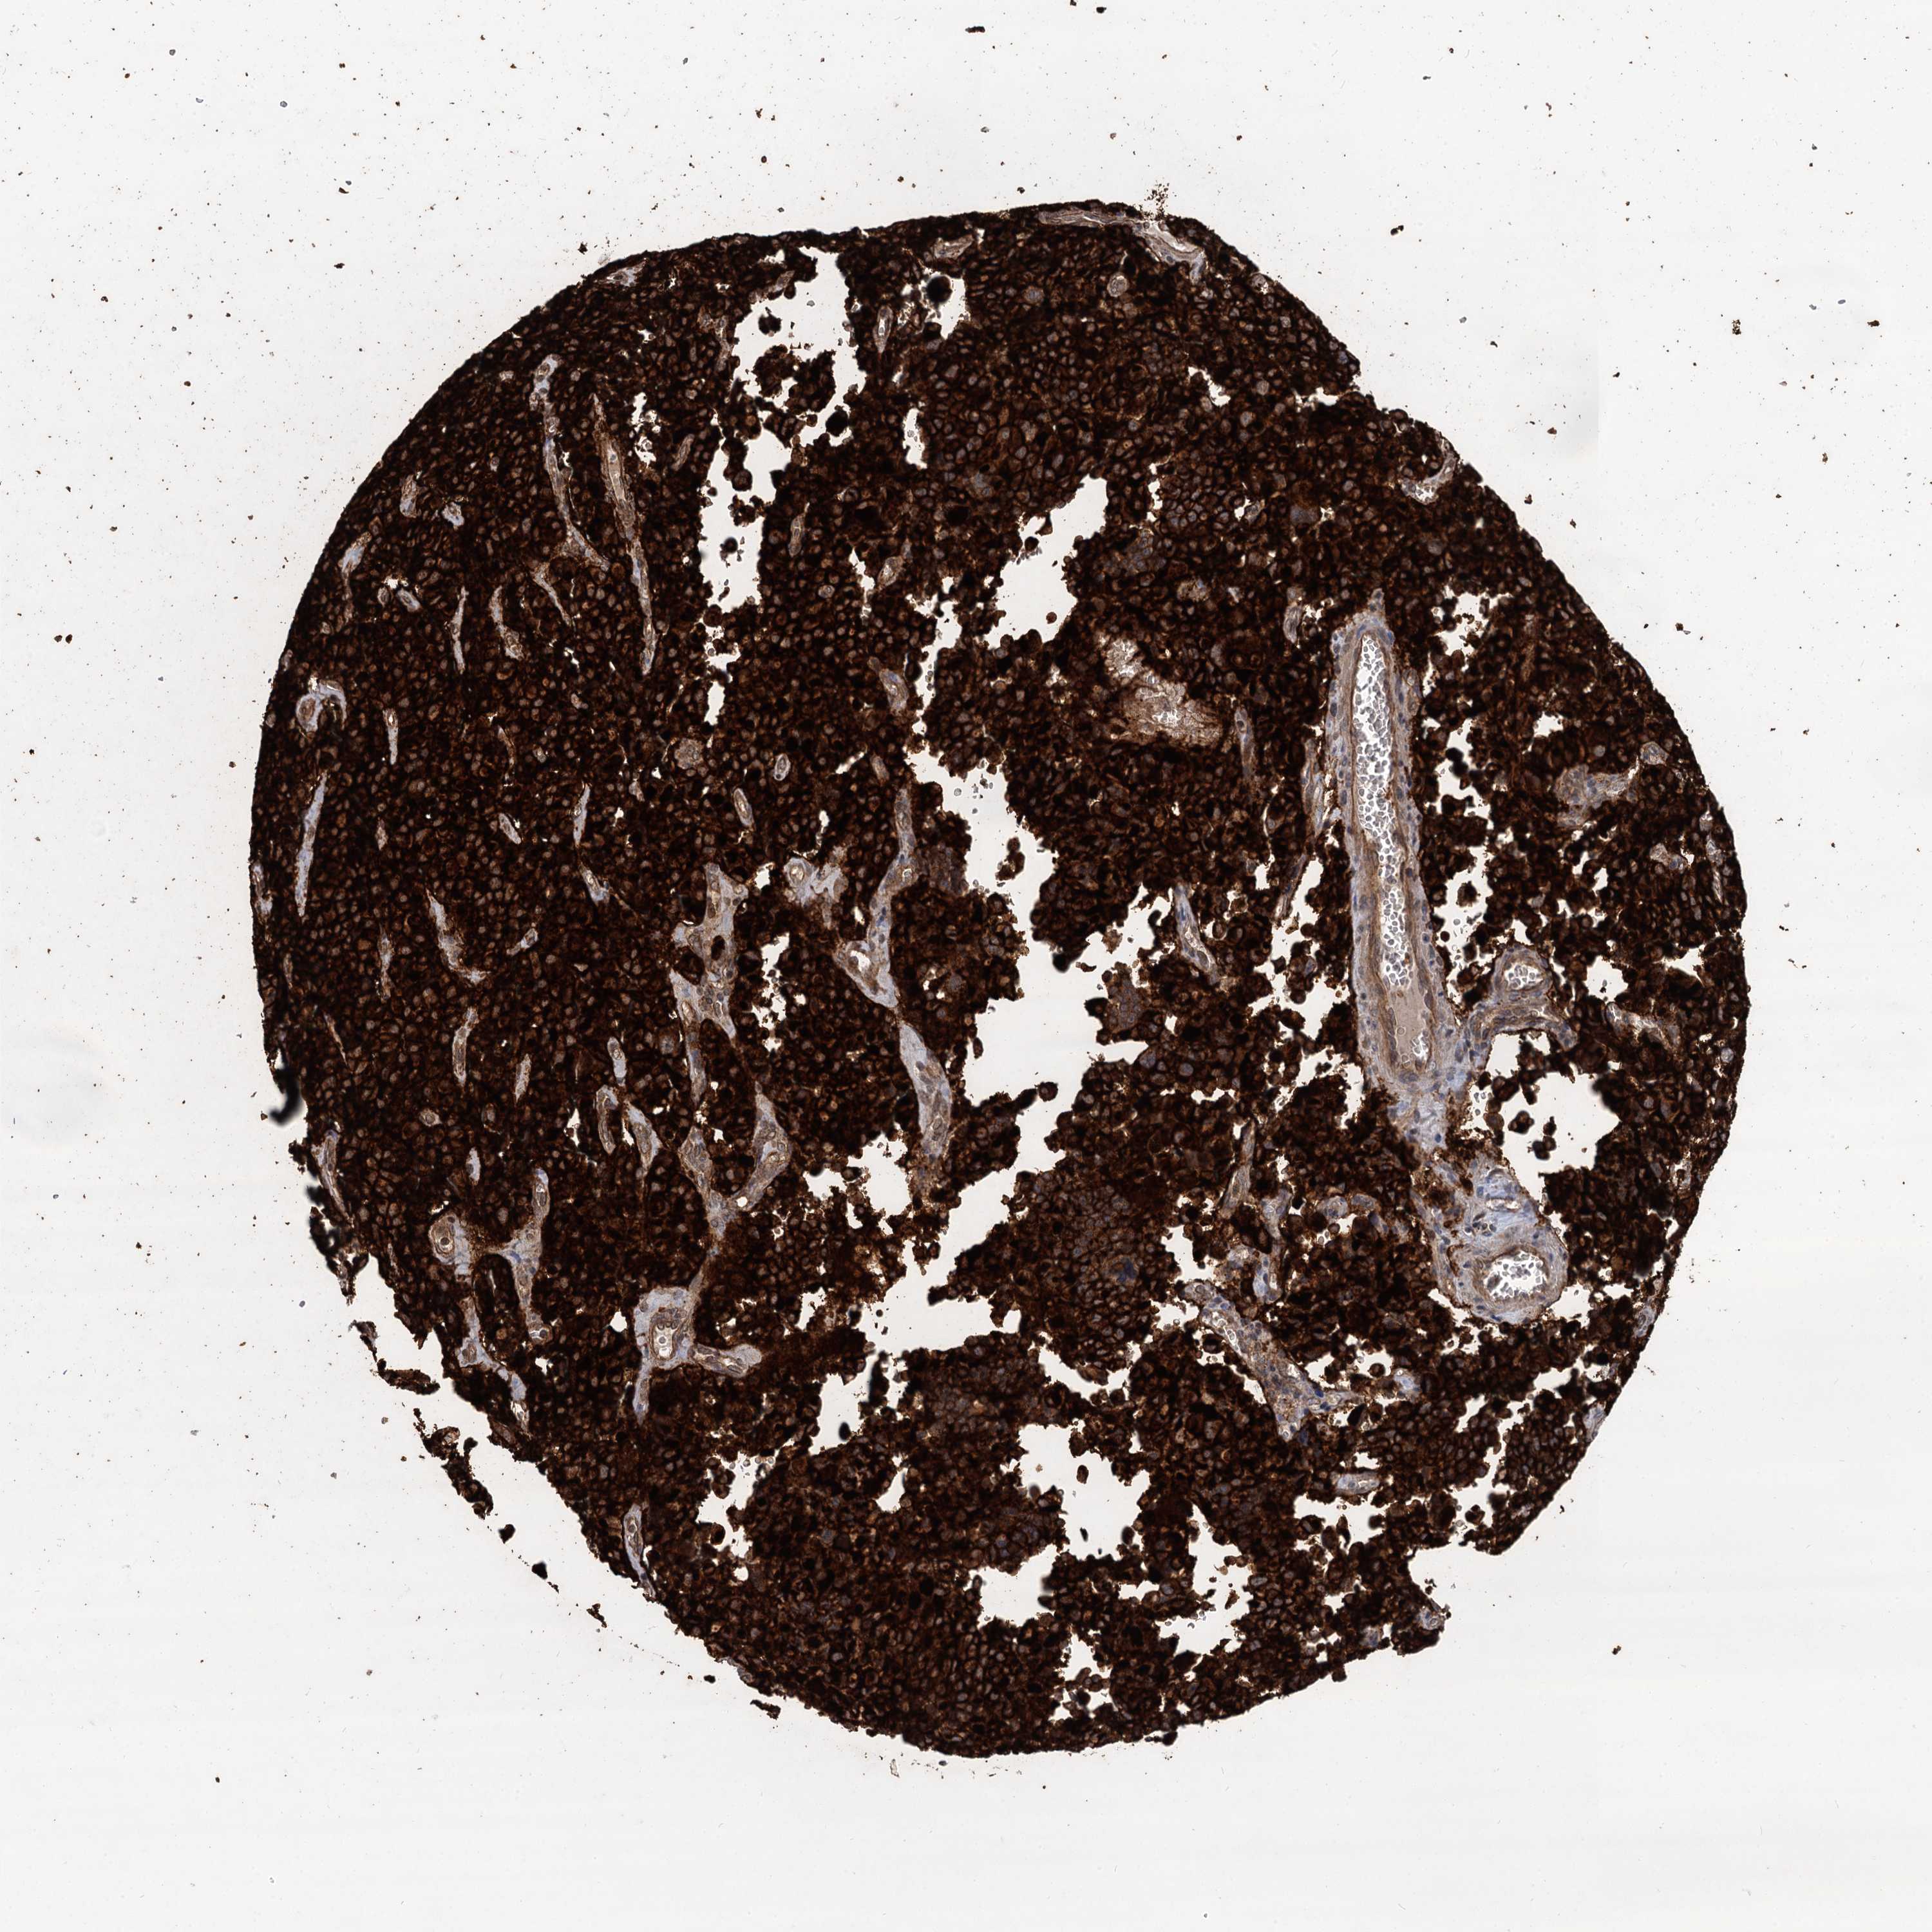

PANCREATIC CANCER - Protein expressioni

A mouse-over function shows sample information and annotation data. Click on an image to view it in a full screen mode. Samples can be filtered based on level of antibody staining by selecting one or several of the following categories: high, medium, low and not detected. The assay and annotation is described here.

Note that samples used for immunohistochemistry by the Human Protein Atlas do not correspond to samples in the TCGA dataset.

Antibody stainingi

Antibody staining in the annotated cell types in the current human tissue is reported as not detected, low, medium, or high, based on conventional immunohistochemistry profiling in selected tissues. This score is based on the combination of the staining intensity and fraction of stained cells.

Each image is clickable and will lead to virtual microscopy that enables deeper exploration of all samples and also displays staining intensity scores, fraction scores and subcellular localization as well as patient and tissue information for each sample.

Antibody HPA039807

Staining

High

Medium

Low

Not detected

Intensity

Strong

Moderate

Weak

Negative

Quantity

>75%

75%-25%

<25%

None

Location

Nuclear

Cytoplasmic/membranous

Cytoplasmic/membranous,nuclear

Adenocarcinoma, NOS